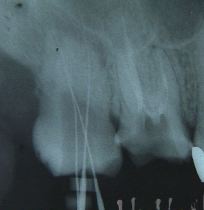

約5か月経ってから根管治療を行います.

歯牙移植

移植から約7か月で治療が完了です.